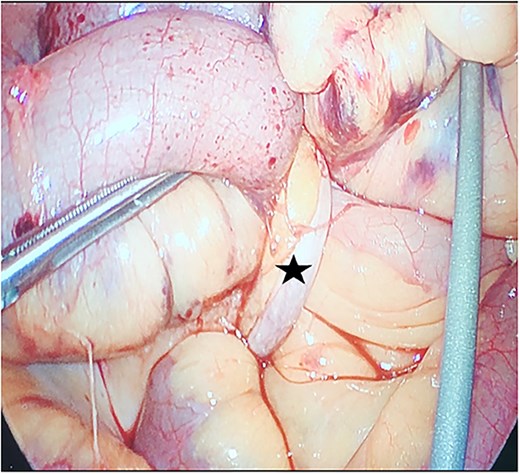

Due to imaging findings and ongoing clinical concern for impending bowel compromise, the patient was taken to the operating room urgently and underwent a diagnostic laparoscopy. Intraoperatively, the appendix was found to be inflamed at the tip and it was adherent to the lateral abdominal wall (Fig. 3). The appendix was forming a band encircling a loop of small bowel, resulting in a mechanical obstruction (Fig. 4). Lysis of the adhesions was performed, successfully freeing both the appendix and the entrapped segment of small bowel (Fig. 5). The involved bowel segment appeared hemorrhagic but was not frankly ischemic, therefore bowel resection was not needed. A laparoscopic appendectomy was subsequently performed. The excised appendix measured 7 cm in length (Fig. 6). The obstruction was resolved, and the patient tolerated the procedure well. She had an uncomplicated postoperative recovery. She started passing gas and tolerated oral intake on postoperative day 1. She was discharged on postoperative day 2. At her follow-up clinic visit, her incisions were well-healed. She reported normal bowel function, no abdominal pain, and was gradually resuming her regular activities. Overall, she was recovering well, with no concerns.

The appendix forming a band around the small bowel, causing small bowel obstruction (star).